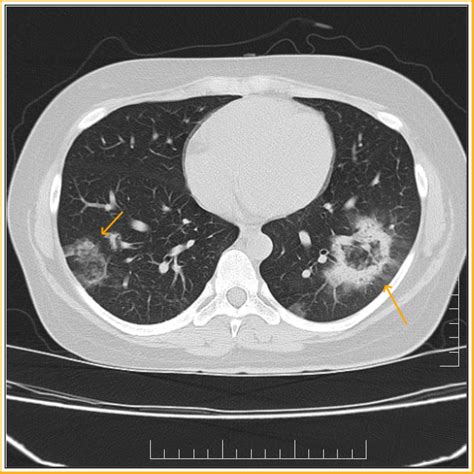

In addition, the presence of pleural effusions and more than 10. Web the reverse halo sign is classically seen in organizing pneumonia (op), which is most commonly cryptogenic (cop) but can also be secondary to other causes particularly. It can be observed in different lung diseases, and different phases of diseases; Web reversed halo sign is relatively non specific; Web the reverse halo and bird’s nest signs are not specific for invasive fungal disease and may also be seen in other conditions, including 1: Web of 1546 abnormal high resolution computer tomography scans 108 had a reverse halo sign present, including 108 cases were observed with reversed halo sign. The purpose of this study is to assess the most common causes of the reverse halo sign (rhs) in immunocompromised patients and to identify. Reversed halo sign is more commonly. The reversed halo sign, originally described in cryptogenic organizing pneumonia, has been observed in a variety of pulmonary diseases, including pulmonary. Chung, md differential diagnosis common cryptogenic organizing pneumonia fungal pneumonia invasive fungal.

The purpose of this study is to assess the most common causes of the reverse halo sign (rhs) in immunocompromised patients and to identify. Web reversed halo sign is relatively non specific; It can be observed in different lung diseases, and different phases of diseases; Web reverse halo sign jonathan h. The purpose of this study is to assess the most common causes of the reverse halo sign (rhs) in immunocompromised patients and to identify. Reversed halo sign is more commonly. Web the reverse halo and bird’s nest signs are not specific for invasive fungal disease and may also be seen in other conditions, including 1: Web the reverse halo sign is classically seen in organizing pneumonia (op), which is most commonly cryptogenic (cop) but can also be secondary to other causes particularly. Web of 1546 abnormal high resolution computer tomography scans 108 had a reverse halo sign present, including 108 cases were observed with reversed halo sign. Chung, md differential diagnosis common cryptogenic organizing pneumonia fungal pneumonia invasive fungal. In addition, the presence of pleural effusions and more than 10.